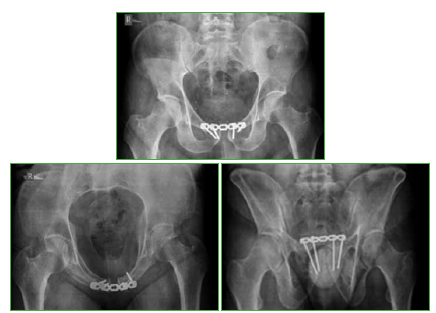

Figura 3.

Control radiológico posoperatorio.

El paciente fue operado dentro de las 24 h del ingreso en nuestra institución: reducción abierta y osteosíntesis en la sínfisis pubiana a través de un abordaje tipo Pfannenstiel (duración aproximada 50 min). Como se trató de un procedimiento abierto, solo a nivel de la sínfisis pubiana, no se utilizó mesa de tracción o tracción esquelética, ni tampoco se realizaron maniobras intempestivas para lograr la reducción obtenida, que generaran o movilizaran trombos. Al concluir la cirugía, se retiraron los campos quirúrgicos y se observó, en la piel del miembro inferior izquierdo, una coloración marmórea, con buena movilidad y sin dolor. A los 30 min, en la habitación, se constató la pérdida de movilidad por debajo de la rodilla e hipoestesia, por lo cual inmediatamente se solicitó una evaluación a los médicos de cirugía vascular, quienes sospecharon flegmasia cerúlea dolens, debido a la evolución tórpida (Figura 2). El informe del eco-Doppler indicó: “trombosis oclusiva total de vena ilíaca externa, femoral común, superficial y profunda, importante edema de tejido celular subcutáneo y permeabilidad arterial en todo su recorrido”. Una vez confirmado el diagnóstico, se inició el tratamiento anticoagulante. A las 24 h del episodio, la perfusión mejoró de forma sustancial. Al cuadro inicial se le agregó un marcado aumento del volumen del miembro como consecuencia de la estasis venosa y linfática. El paciente fue movilizado para el control radiológico posoperatorio (Figuras 3 y 4).